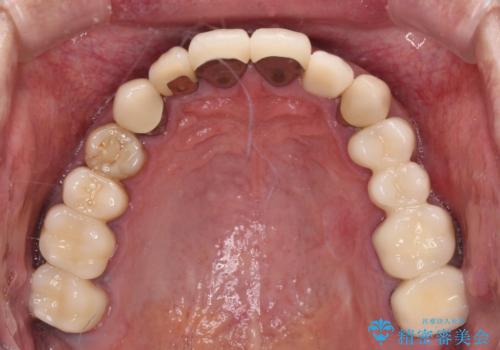

下顎の部分矯正を行ってから奥歯の補綴治療とインプラント治療

- 抜歯した歯や抜歯が必要と思われる歯を放置したため、奥歯に不快を感じているとのことで来院された患者様です。

右下は奥歯が抜歯したスペースを塞いでしまい、左下はブリッジの支台歯の1つが破折している状態でした。

また、下顎前歯にはスペースがあり、コンポジットレジンでスペースを閉じている状態だったので、前歯のスペースを解消しつつ、奥歯にスペースを獲得するよう矯正治療を行うこととしました。

並行して左下にはインプラントを埋入し、上顎臼歯部の気になる部分も根管治療などを進めて行き、矯正治療を終えると同時に補綴治療を行うこととしました。